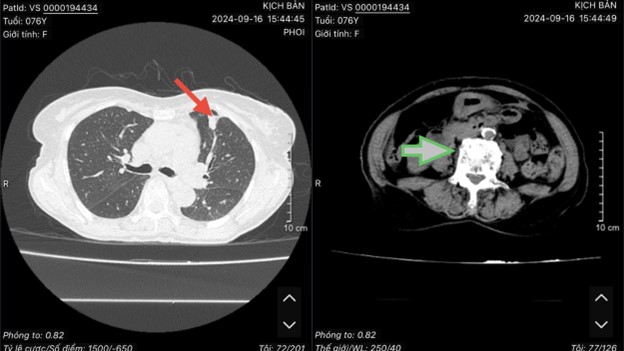

Tháng 12/2021, bệnh nhân xuất hiện đau ngực trái tăng dần kèm ho khan, khó thở nhẹ, ăn uống kém, không sốt. Đi khám tại Bệnh viện Bạch Mai được chụp cắt lớp vi tính lồng ngực phát hiện: Thuỳ trên phổi trái có khối đặc kích thước 20x21mm, bờ không rõ, co kéo xung quanh, nhiều nốt di căn phổi hai bên, thân đốt sống, dịch màng phổi bên phải 36mm, bên phải 20mm, dịch màng ngoài tim.

Hình 1: Hình ảnh trước điều trị: Ở thuỳ trên phổi trái có khối đặc kích thước 20x21mm,nhiều nốt di căn phổi hai bên, dịch màng phổi hai bên.